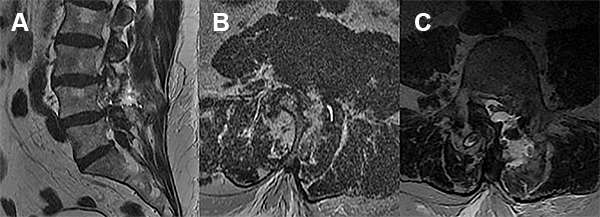

Se decidió internación para valoración clínica y por imágenes. Por resonancia se evidenció colección de LCR en el sitio de la reparación dural (fig. 1).

Figura 1

Se decidió re explorar la herida con abordaje MIIS mediante la cual se coloca un parche dural. Se indica el alta 48 hs de postoperatorio con buena evolución clínica asintomático.